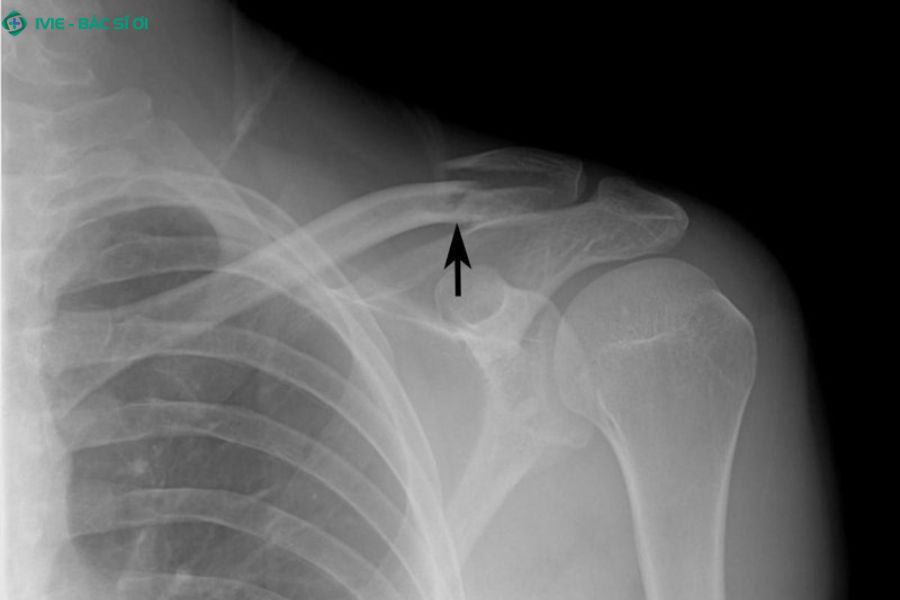

Gãy xương

Gãy xương đòn và xương bả vai, gây đau dữ dội và hạn chế cử động tay

Gãy xương ở vùng vai - cổ là một trong những nguyên nhân có thể gây đau cổ vai gáy bên trái, đặc biệt khi tổn thương xảy ra ở xương đòn hoặc xương bả vai.

Gãy xương đòn (xương quai xanh): Xương đòn là phần nối giữa xương ức và vai, giúp vai cử động linh hoạt và bảo vệ các cơ quan quan trọng như phổi và mạch máu. Khi bị ngã, tai nạn hoặc va chạm mạnh, xương này có thể gãy, khiến vai đau nhức, sưng, bầm tím và khó nâng tay.

Gãy xương bả vai: Xương bả vai có hình tam giác, nằm phía sau vai và giúp kết nối cánh tay với khung ngực. Khi bị tác động mạnh, chẳng hạn do tai nạn hoặc chấn thương thể thao, xương này có thể gãy, gây đau dữ dội và sưng ở vùng sau vai, khiến việc cử động tay trở nên rất khó khăn.